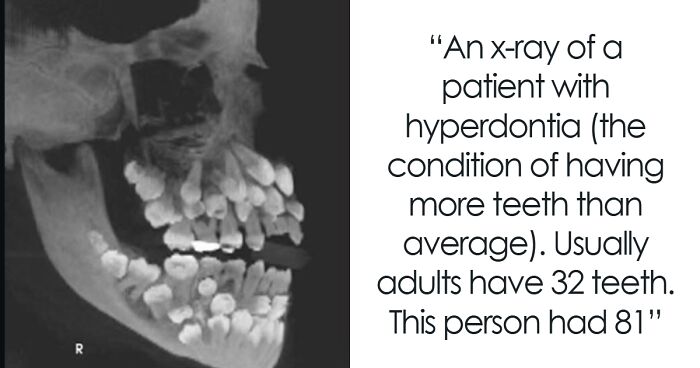

I Work At A Vet School